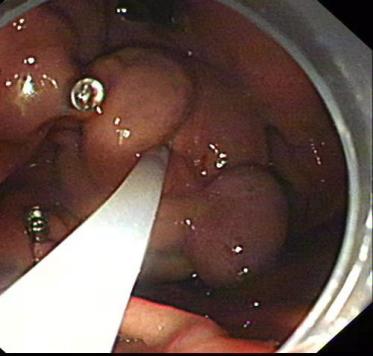

⑧静脉套扎及组织胶注射

肝硬化食管静脉曲张一旦破裂往往造成致命的大出血。内镜下食管静脉曲张套扎术(EVL)是对食管下段曲张静脉逐一结扎,使其缺血狭窄、静脉闭塞,增加静脉周围纤维覆盖,从而使曲张静脉消失,达到止血和预防再出血。

食管静脉曲张

食管静脉破裂出血

食管静脉曲张套扎进行中

食管静脉曲张套扎进行中近观

食管静脉曲张套扎恢复后

EVL是抢救食管静脉曲张破裂大出血、预防再出血的首选方法,该技术具有快捷、简单、并发症少、疗效高的特点 。EVL是治疗食管静脉曲张的一种新技术和新方法,我院消化内科开展EVL 1O年,多位教授具有丰富临床经验,每年救治了无数肝硬化食管胃底静脉曲张破裂大出血患者生命。